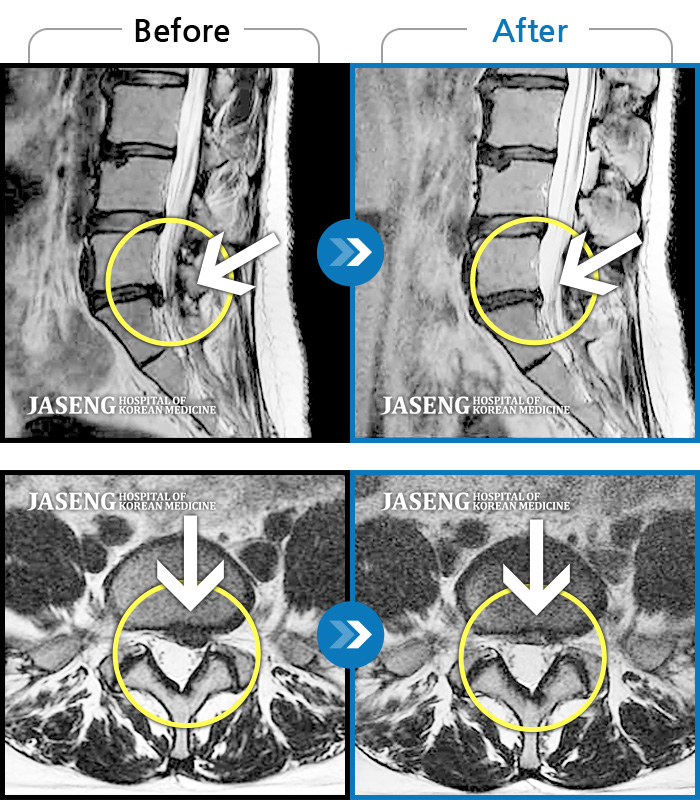

허리디스크

잠실 · 한상욱 원장

허리통증과 함께 좌측 엉치, 허벅지, 종아리 후면으로 저림이 심하여 걷기가 힘들어요.

촬영시기

2021.09.14 ~ 2022.05.14

2022.05.24

조회수 149